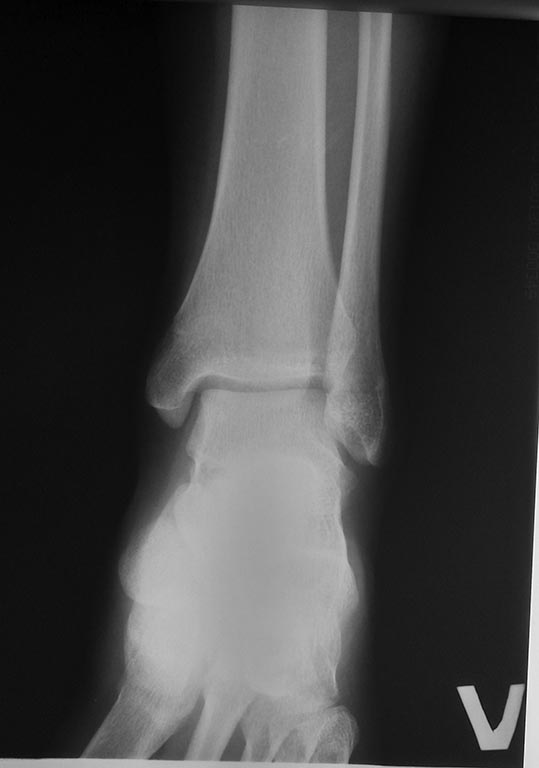

Лучше подождать! Удлинить -то можно, но восстановить конгруэнтность- вряд ли : деформирована и таранная кость. Надеюсь 2 см это опечатка?,

Сустав деформирован конечно, но уже 2 года, а боли пол года. По снимку напрашивается остеотомия. Сделайте скиаграмму, вырежьте клин и соберите снова. Так вы уменьшите нагрузку на голеностопной сустав. Но даст ли корригирующая надлодыжечная клиновидная остеотомия большеберцой эффекта трудно сказать? Так как основное показание это боль в голеностопном суставе,а не нарушение конгрунтности.

Мне кажется, что хороший объём движений в голеностопном суставе сохраняется за счёт снижения опорной нагрузки на латеральную деформированную часть большеберцово-таранного сочленения (малоберцовая кость, как распорка). Поэтому и инконгруэнтность клинически почти не проявляется. Любая коррекция ( остеотомия, удлинение б/берцовой, резекция м/ берцовой) может привести к ухудшению ситуации.

После коррекции суставной площадки большеберцовой кости у нас по прежнему будет сохраняться относительное переудлинение малоберцовой кости с последующим нарастанием клиники невропатии малоберцового нерва. Девочка к нам и обратилась с болями в области колена (в области головки малоберцовой кости) и стопе.

В принципе при удлинении изолированно большеберцовой кости посредством остеотомии в н/3 можно устранить и деформацию суставной площадки.

Оставлять как есть, как то не очень, деформация голеностопного сустава по моему мнению будет только нарастать и дестабилизировать сустав.

Имеющаяся импрессия (или более раннее замыкание росткового хряща) латеральной части эпифиза б/берцовой кости привели к угловой деформации её суставной поверхности на вальгус. Смещению вслед таранной кости мешает лишь более длинная м/берцовая кость. Любое из предлагаемых укорочений м/берцовой или удлинений б/берцовой костей приведёт к вальгусной деформации голеностопного сустава, а желаемый равномерный контакт суставных поверхностей - к манифестации инконгруэнтности и артроза. Исход вполне предсказуемый! Предлагаемая Ниязом клиновидная остеотомия биомеханически вроде более обоснована, однако в конкретном случае действительно сложна , и результат непредсказуем.

Из-за травмы ростковой зоны большеберцовая отстала от нормального развития, и эта диспропорция костей привела к тому, что малоберцовая принимает активное участие в распределении нагрузки. Дистальное сочленение лучше выдерживает нагрузку и поэтому латеральная лодыжка гипертрофируется. Продолжающаяся нагрузка выталкивает из ложа головку малоберцовой вверх, переводит в подвывих и поэтому появляется боль с характерным выступающим контуром головки!